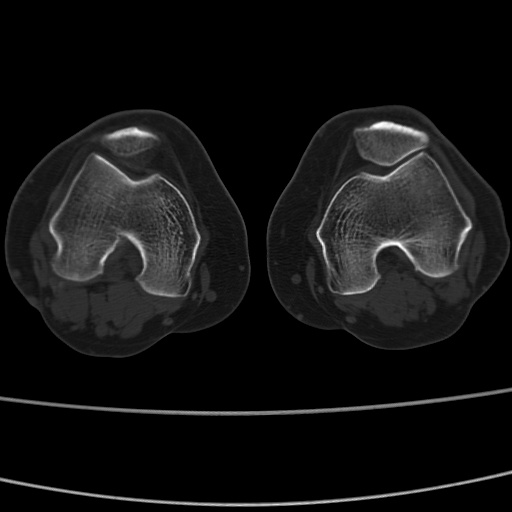

女性,50岁。【请提供患者临床症状体征】

右膝关节退行性改变,关节游离鼠。

右膝关节退行性改变,滑膜黏液囊钙/骨化并游离。

右膝关节退行性改变